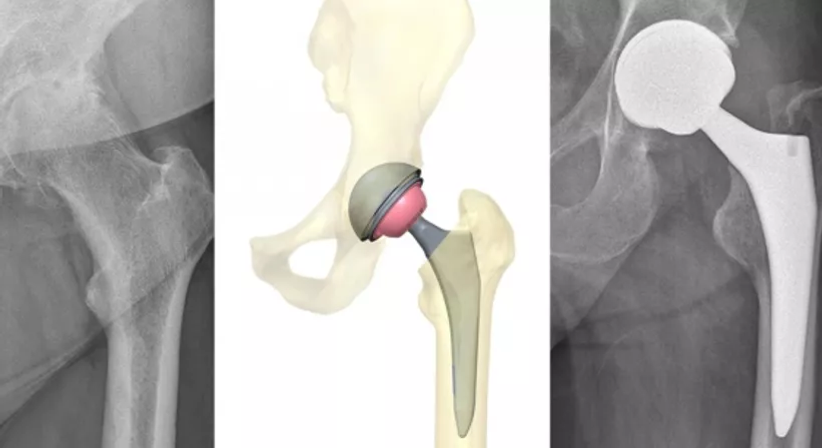

Die Implantation einer Hüftprothese (künstliches Hüftgelenk) erfolgt in den meisten Fällen bei einer konservativ austherapierten und schmerzhaften Coxarthrose (Hüftgelenksarthrose). Weitere Gründe einer H-TEP (= Hüft-Hüfttotalendoprothese) stellen die Hüftkopfnekrose oder die Folgen einer Verletzung der Hüfte dar.

Im Rahmen einer Hüftoperation werden alle Bestandteile des geschädigten Hüftgelenks durch künstliche Materialien ersetzt. Dabei kommen Implantate aus Titanlegierungen und Keramik zum Einsatz, welche dem internationalen Standard entsprechen.